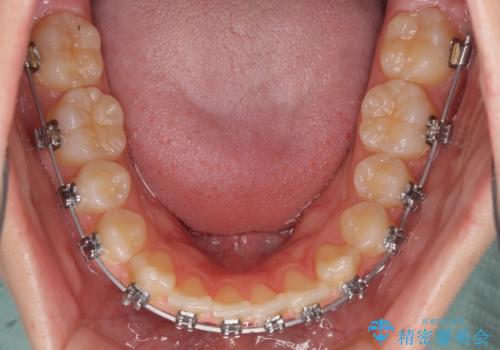

- メタルブラケット

- 2年3ヶ月

当初は1年半程度の治療期間を想定していましたが、上下の正中を合わせていく過程で奥歯の咬みにくさが続いてしまい、2年以上の治療期間を要することとなりました。